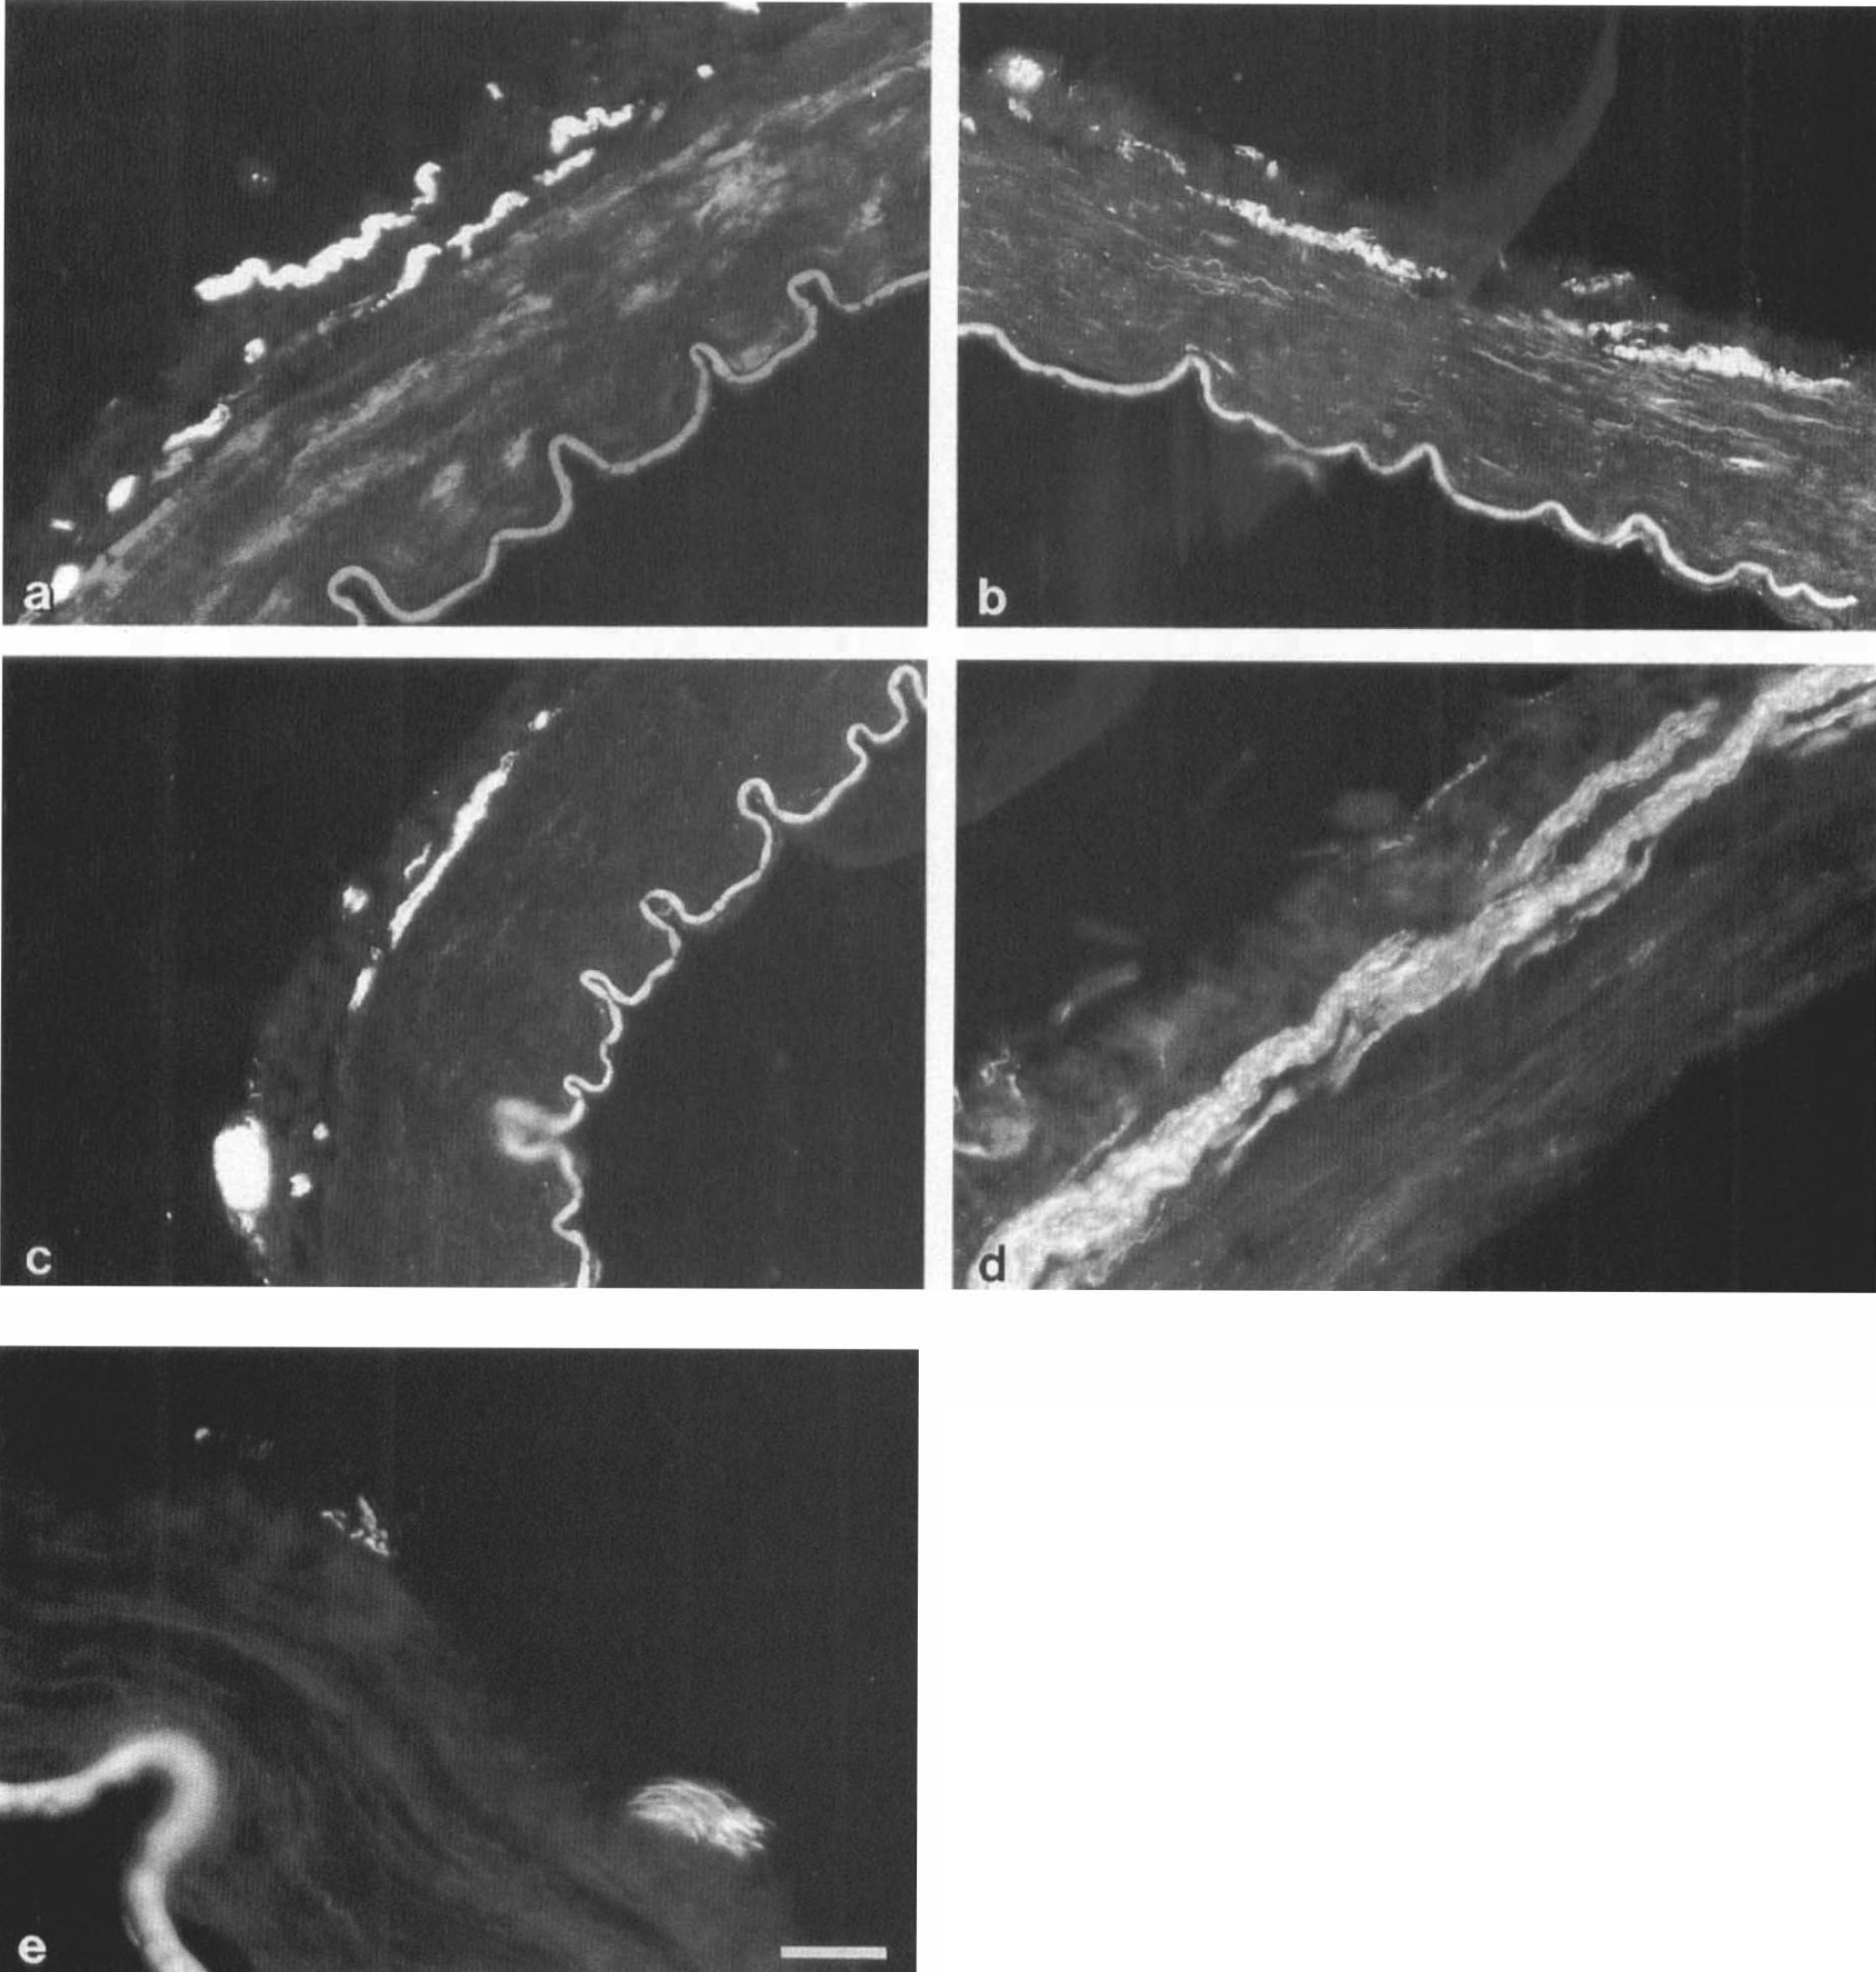

Figure 6 shows representative staining results. Nerve staining by each antibody was observed in all arteries investigated. The PGP 9.5 staining was intense and showed nerves throughout the adventitia. At the adventitial–medial border the nerves were often oriented in a transverse direction. In the PCom these nerves were of a large caliber. Cross sections through nerves outside the adventitia indicated a longitudinal arrangement. The TH staining was less intense than PGP 9.5. However, nerves could again be seen throughout the adventitia, including at the adventitial–medial border. NF staining by R39 was bright and similarly distributed. In contrast, nerve fibers stained by RT97 were located only in paravascular nerve bundles.

Transverse cryostat sections of several cerebral arteries

The number of sections quantified was too low to perform statistics. However, the results confirm the measurements of high nerve densities in the PCom and P2 segment made on whole-mounts of these specimens. Furthermore, results suggest that TH- and R39-positive nerves constitute subpopulations of PGP 9.5 stained nerve plexuses.